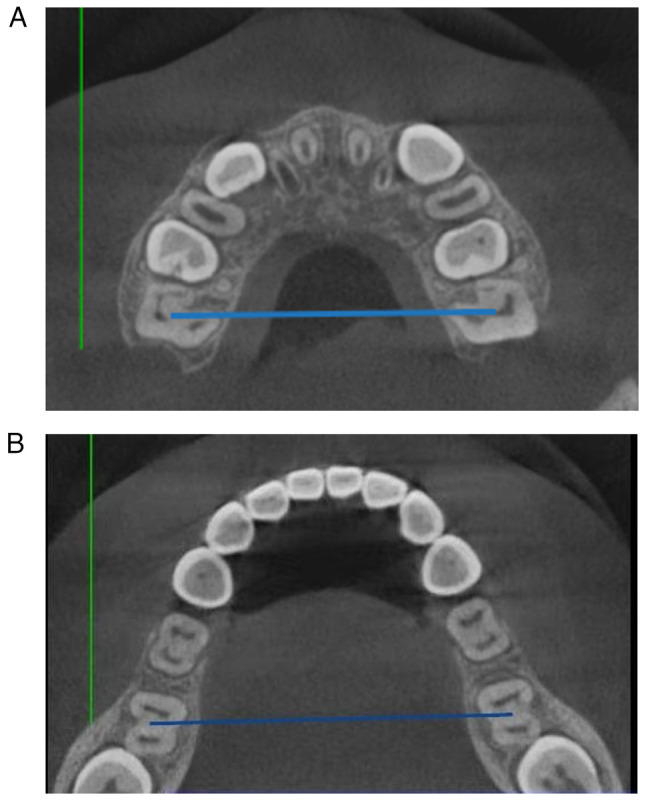

The best timing for treating adolescent patients with skeletal class III malocclusion is still unclear. The present study aimed to explore variations in the efficacy of rapid expansion combined with maxillary protraction therapy in patients with skeletal class III malocclusion at different growth and development stages. Clinical records of 45 patients with skeletal class III malocclusion who underwent rapid expansion combined with maxillary protraction therapy from January 2019 to June 2022 were included in the present study. Based on the cervical vertebral maturation method (CVM), the patients were retrospectively divided into three groups: Pre-pubertal (CVM stages I-II, n=15), pubertal (CVM stage III, n=15) and post-pubertal (CVM stages IV-VI, n=15). Lateral head radiographs before and after the treatment and various bone, dental and soft tissue measurements were compared between groups to assess the differences in treatment effects. The results of the intra-group comparison before and after the treatment showed that the dental and bone indicators, such as A Point-Nasion-Point B angle, sella-nasion-A point angle, sella-nasion-B point angle, mandibular plane angle, A Point-VR plane and anterior Nasal-VR plane (ANS-VR) were significantly different compared with those before treatment in all three groups of patients (P<0.05). The posterior Nasal-VR plane (PNS-VR) changed significantly in the pre-pubertal and pubertal groups (P<0.05), but there was no significant change in the post-pubertal group. The Glabella-Pronasale-Pogonion of soft tissue and Sella-Nasion-Nasion-Bs Point angle decreased significantly post-treatment in the three groups, while the Sella-Nasion-Nasion-Sn Point angle increased (P<0.05). Intergroup comparisons before and after treatment showed that there was no significant difference in the post-treatment indexes between the pre-pubertal and pubertal groups. The changes in ANS-VR and PNS-VR values before and after treatment were statistically significant between the post-pubertal and the other two groups (P<0.05). In conclusion, rapid expansion combined with maxillary protraction therapy has the best treatment effects in patients in the pre-pubertal and pubertal stages and is associated with significant skeletal effects and less alveolar response. Although the skeletal treatment effects are less favorable in patients in the post-pubertal stage with more pronounced alveolar responses, the treatment can still provide appropriate compensation for facial deformities and reduce the likelihood of orthognathic surgery.